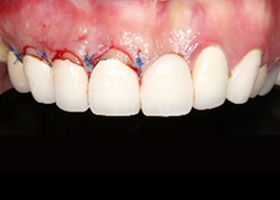

右側前牙進行牙冠增長術,調整牙齒比例。